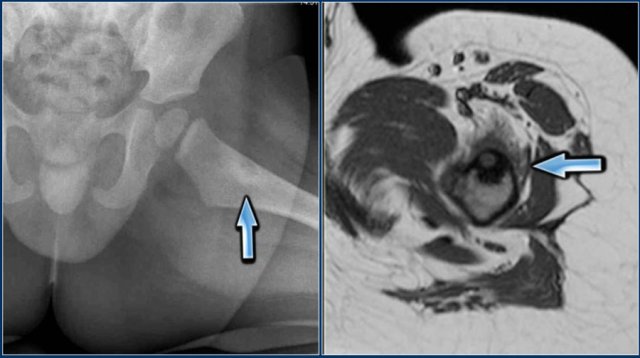

Brodie's abscess

A subtype of osteomyelitis which is typically seen in children is a Brodie's abscess.

It is a subacute osteomyelitis with intraosseous abscess formation.

The only complaint can be pain.

Fever and inflammatory markers may be absent.

The abscess is usually located in the metaphysis of long bones, but may be located in the epiphysis in young children.

On x-ray there is a sharp defined oval lytic lesion with or without a sclerotic rim, with its long axis parallel to the long axis of the bone (see figure).

On MRI the lesion is hyperintense on T2WI. There is joint effusion and only minimal edema in the surrounding musculature.